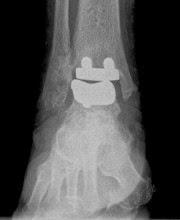

Decidí implantarle una prótesis por los siguientes motivos fundamentalmente:

Primero es mayor de 60 años y, por lo tanto se cumple la expectativa de no tener, posiblemente, que recambiar la prótesis cuando ésta se deteriore.Segundo la demanda funcional normal del paciente es pequeña, es decir, no hace mucho deporte ni tiene un trabajo muy pesado.Y tercero, la calidad del hueso es aceptable y no presenta grandes deformidades.En caso de no cumplirse éstos supuestos hay, lógicamente, otras posibilidades de tratamiento, más adecuadas en cada caso.La principal ventaja de ésta cirugía es que permite recambiar una articulación dolorosa con poca movilidad normalmente, por una nueva con mejor movilidad y sin dolor, en contraposición con la cirugía convencional como por ejemplo, una artrodesis o fusión de la articulación (deja de doler pero se pierde la movilidad).Los inconvenientes principales son el precio que es alto, y la dificultad técnica de la intervención quirurgica.Abajo os muestro las radiografías de antes y después de la operación: